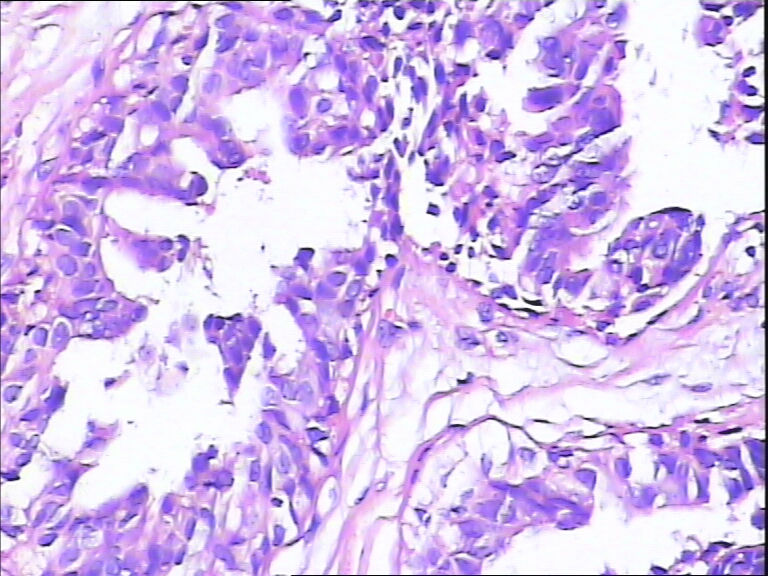

B3862乳腺包块

40岁,发现乳腺包快5月

标签:UDH ADH

觉得像UDH,做CK5,P63,UDH CK5腺上皮阳性,ADH CK5腺上皮阴性

ADH

DIN1b

导管不典型增生,不够导管内癌,做一做免疫组化就一目了然了

感觉不是普通型增生(UDH),应该到ADH或DCIS  免疫组化 ck5/6  34bE12

导管内癌

觉得不够癌

考虑导管内原位癌  需做组化确诊

Quality of the slides is not good.

More like UDH